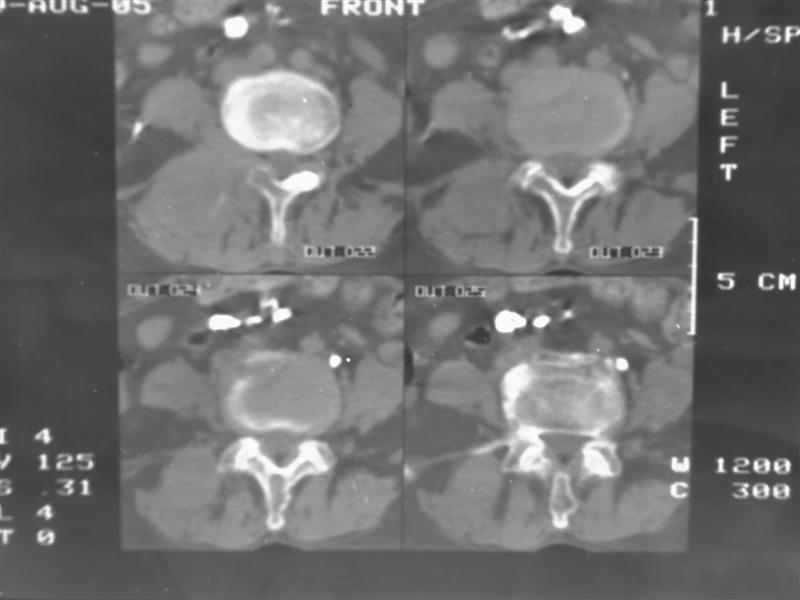

以下是引用老爱克斯新网客在2007-9-27 17:59:00的发言:[br]多个椎体及椎弓跟骨质破坏,并见软组织肿块,符合转移瘤改变,

以下是引用wqs571018在2007-9-27 16:48:00的发言:[br]支持:多发病变,骨质破坏伴软组织块影,符合转移.